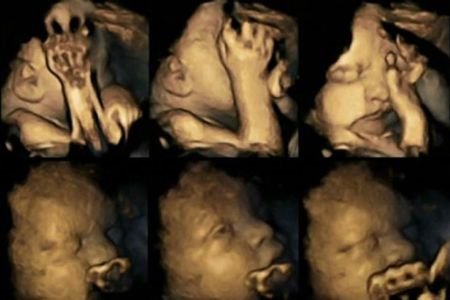

Posmatrajući bebe uz pomoć 4D ultrazvuka, istraživači sa Univerziteta Durham i Lankaster su otkrili da su fetusi, čije mame puše u trudnoći, imaju znatno veću stopu pokreta usta od normalne stope pokreta.

Naučnici naglašavaju da razlog za to može biti centralni nervni sistem kod fetusa, koji kontroliše pokrete, a koji je zbog duvanskog dima u ovom slučaju usporen i nerazvijen.

Doktorka Nađa Rajsland sa Durham Univerziteta, koja je vodila istraživanje, pregledala je 20 budućih mama od kojih su četiri pušile u proseku 14 cigareta dnevno.

Nakon što je proučila očitavanja iz 24, 28, 32. i 36. nedelje trudnoće, primetila je da deca majki koje nisu ostavile cigarete češće dodiruju usta i lice od ostalih.